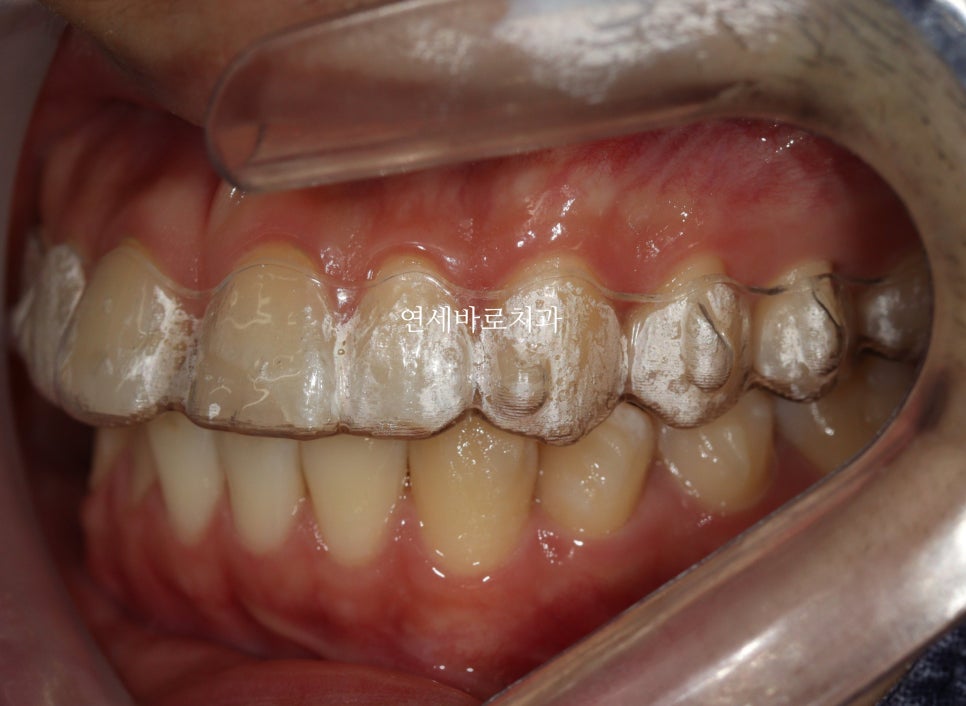

2024년 5월 14일 첫 내원

24.5.14.에 오신 분입니다.

이미 예전에 치아를 다친적도 있어서 치아의 절반이 레진인 상태였습니다.

이미 치아의 크기도 크셨던 분.

여기서 저 공간을 레진 등으로 매꾼다면 더 커지는 치아의 사이즈로 인해 심미적이지 못할겁니다.